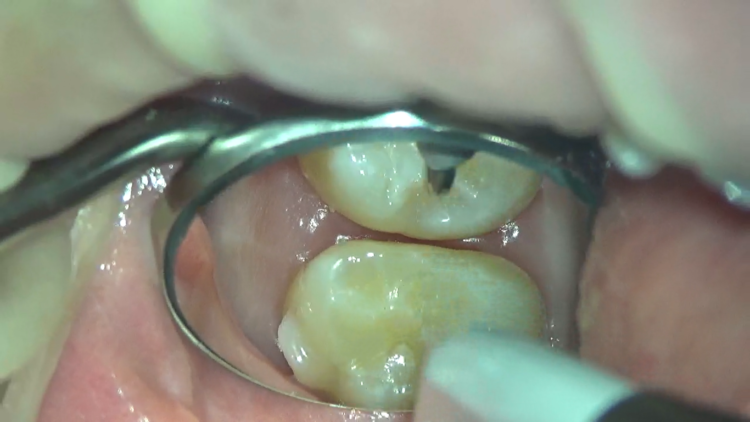

一番奥の歯と、二番目の歯の間です。

物が挟まってしまっていて、隙間が全く見えてない状態。

これは、歯間ブラシを使って取り除いていきます。

だいぶ取れてきました。

フロスも使ってさらに除去。

ついに、取れました!!

こんなに挟まっていても、ご本人は気づいていなかったそうです。

今回も、挟まっていた場所が左上の奥歯。鏡では見にくい場所です。